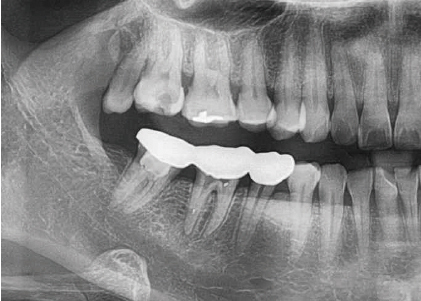

4일 후 #47 치아 근관확장했으나 개통성 확보되지 않음. 다음날 근관길이 측정하여 개통성 확보됨. 치은절제술 가능성 설명함. 근관 내부가 오염되어 있어 칼시펙스(Calcipex)로 근관내 약제 주입함. 다음날 신청인은 우측 하악 부위 앞쪽이 아프고, 욱신거림을 호소함. #47 근관충전하고, 충전 전·후 치근단 방사선 사진 촬영함.

이후 우측 하악 부위 많이 아프다고 호소하여 칼시펙스로 인한 가능성을 고려함. 소론도정(부신호르몬제) 등 약물 처방하였고, 파노라마 촬영 후 칼시펙스 흡수되고 있음을 확인함. 10일 후 온통 살갗까지 아프고, 일을 할 수 없을 정도로 아프며, 진통제를 추가해 먹어도 잠도 한숨도 못자고 혀만 닿아도 아픔을 호소하여 소론도정(부신호르몬제) 등 약물 처방함.

A대학병원 내원하여 콘빔 CT 촬영하고 삼차신경통 진단받고 원인을 제거하기 위한 턱수술 권유받음. B대학병원에서 파노라마 검사상 #47 하방 하치조신경관 내의 방사선 불투과성 물체는 수산화칼슘으로 확인되고, 수산화칼슘에 의한 화학적 손상에서 비롯된 우측 이신경(Mental nerve)의 신경염으로 진단하고, 소론도정(부신호르몬제) 등 약물 처방하여 지속적인 치료 받음. 이후 삼차신경손상으로 3.3% 노동능력상실률 장애 진단받음.

#47 치아에 칼시펙스 약제를 근관내 주입한 후, 신청인이 통증을 호소하면서 내원하였을 당시 치근단방사선 사진과 파노라마 방사선사진을 촬영하고, 칼시펙스가 치근단공을 넘어가서 하치조신경관까지 누출된 것을 확인한 후 소론도 정 등 약물을 투약한 것은 적절하였다고 사료됨. 그리고 이후 계속되는 투약에도 통증이 경감되지 않아 상급 대학병원으로 전원한 것도 적절한 조치였다고 사료됨.